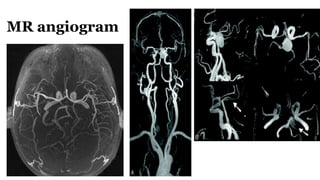

Diagnosis cont..

MR Angio

MR angiogram